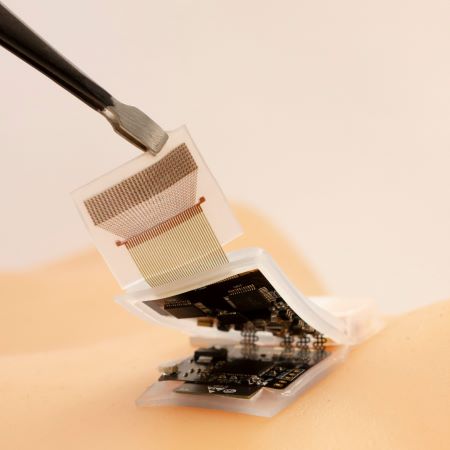

A wearable ultrasonic device to image cardiac function

Researchers have engineered a wearable device that adheres to the skin and uses ultrasound imaging and a deep learning model to produce a dynamic, real-time assessment of cardiac function.